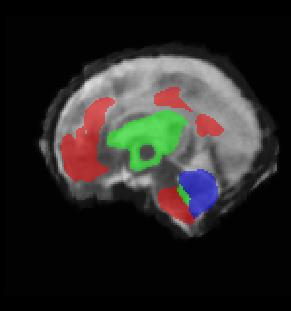

Limiting failures of machine learning systems is of paramount importance for safety-critical applications. In order to improve the robustness of machine learning systems, Distributionally Robust Optimization (DRO) has been proposed as a generalization of Empirical Risk Minimization (ERM). However, its use in deep learning has been severely restricted due to the relative inefficiency of the optimizers available for DRO in comparison to the wide-spread variants of Stochastic Gradient Descent (SGD) optimizers for ERM. We propose SGD with hardness weighted sampling, a principled and efficient optimization method for DRO in machine learning that is particularly suited in the context of deep learning. Similar to a hard example mining strategy in practice, the proposed algorithm is straightforward to implement and computationally as efficient as SGD-based optimizers used for deep learning, requiring minimal overhead computation. In contrast to typical ad hoc hard mining approaches, we prove the convergence of our DRO algorithm for over-parameterized deep learning networks with ReLU activation and a finite number of layers and parameters. Our experiments on fetal brain 3D MRI segmentation and brain tumor segmentation in MRI demonstrate the feasibility and the usefulness of our approach. Using our hardness weighted sampling for training a state-of-the-art deep learning pipeline leads to improved robustness to anatomical variabilities in automatic fetal brain 3D MRI segmentation using deep learning and to improved robustness to the image protocol variations in brain tumor segmentation. Our code is available at https://github.com/LucasFidon/HardnessWeightedSampler.